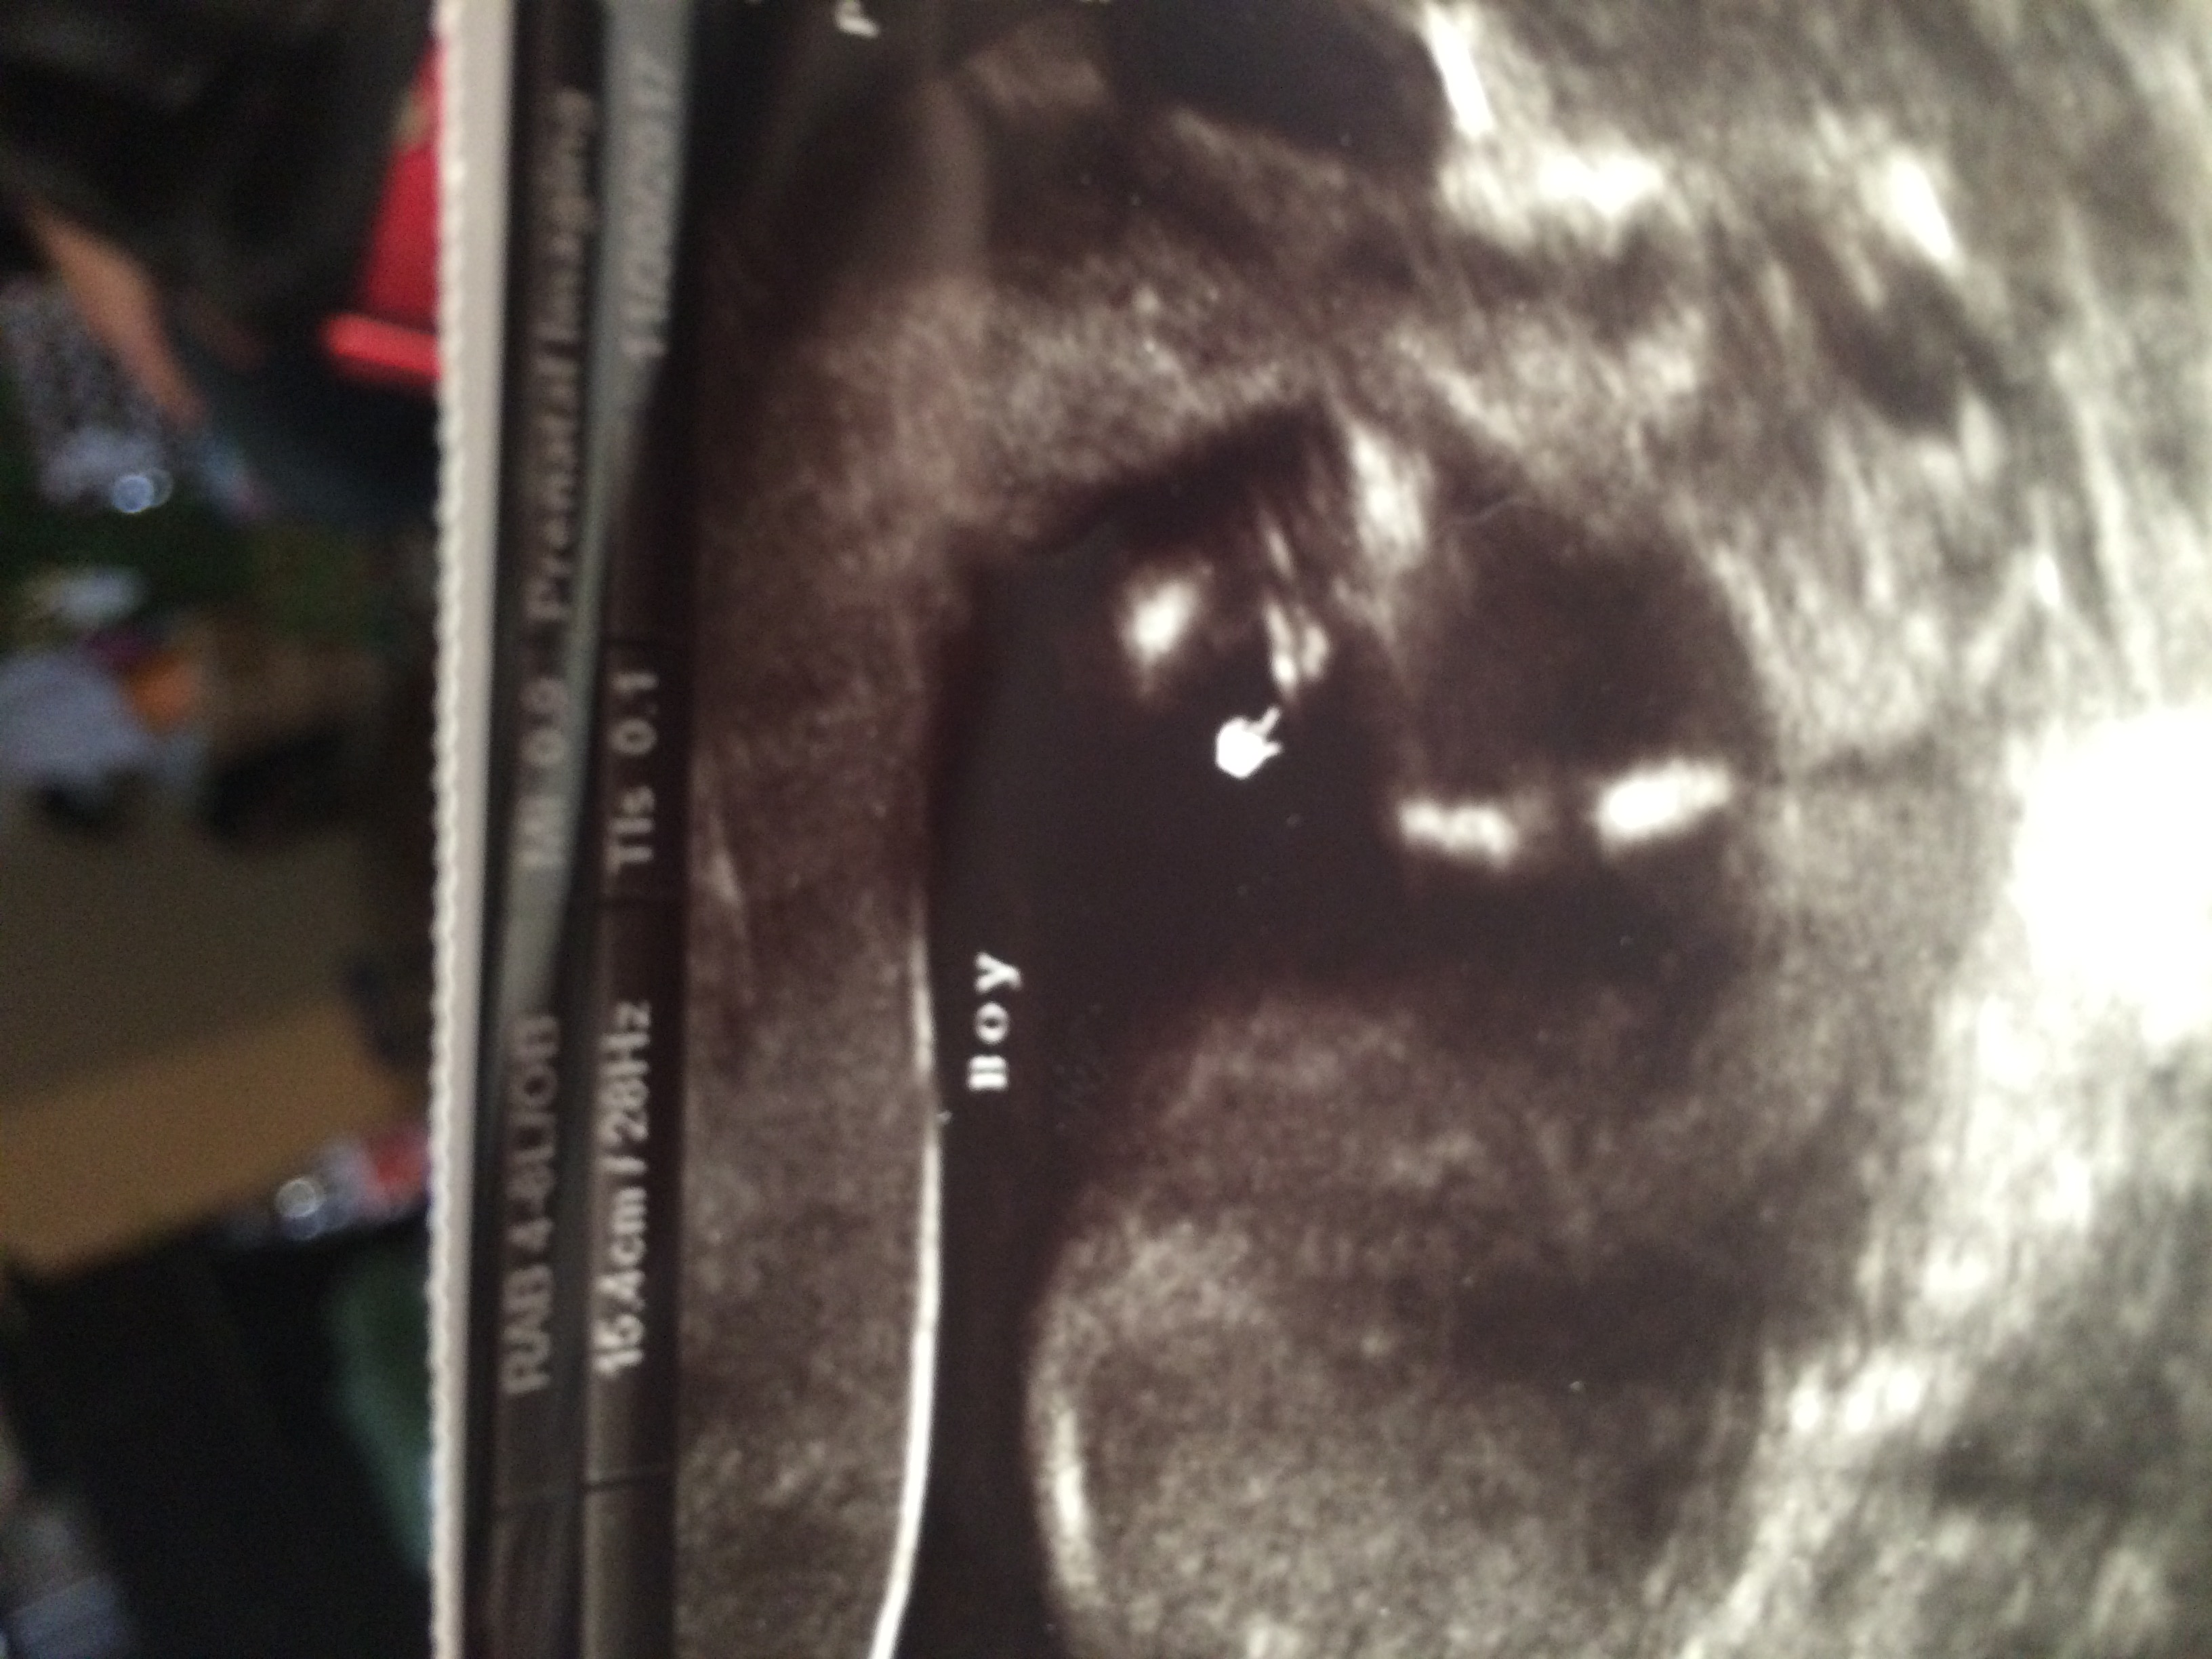

3girls tech says boy but I'm unsure

Hi! I have three daughters and I was very strongly hoping for a boy as this will be my last child. I paid a 3D ultrasound place to do a gender scan at 13 weeks. At the first appointment baby kept its legs closed the entire time. Second appointment was the same story. The tech said to wait in the waiting room while she got the next patient and she would check me again real quick but if baby wouldn't show she would have to reschedule me again. Me and my bf were very disheartened and the tech was clearly a little frustrated. Since we were doing a reveal she told us to close our eyes. She said she finally got a good angle and sent us on. I'm worried it was rushed and she didn't get a great look. She was super sweet and I'm really hoping it's a boy but I'm scared to get too excited. I feel like because it's so early it could just be a nub? I'm not sure, what do you think? I appreciate any input! Attachment 38370